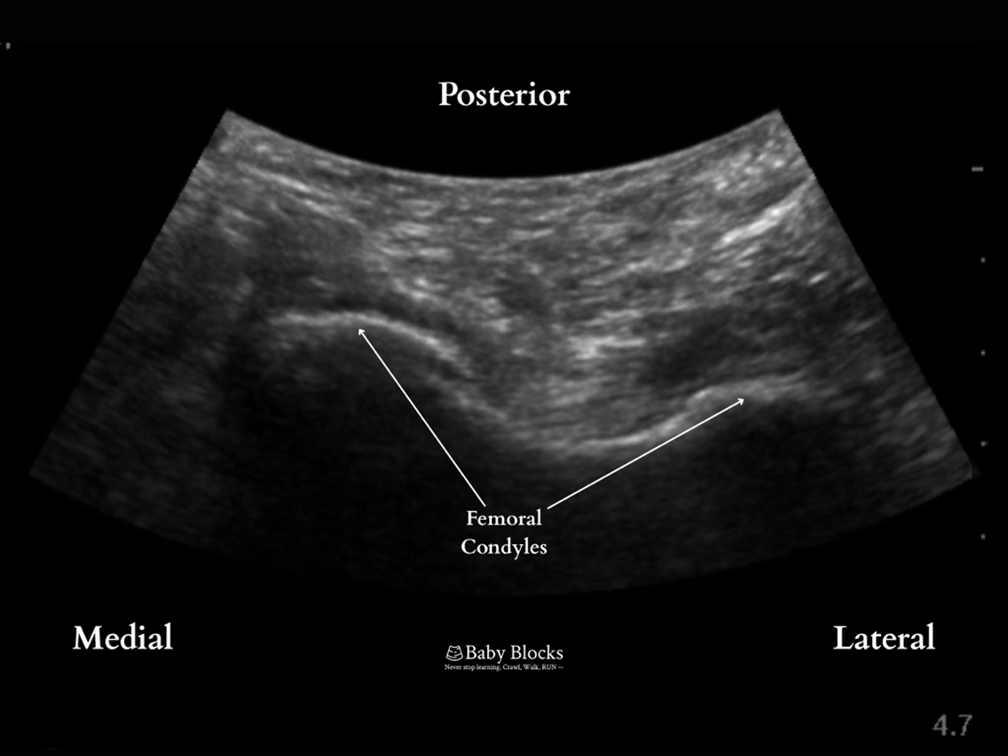

Relevant Anatomy: femoral condyles, femur, muscles, popliteal artery and vein

Lateral border: femur anterior to the popliteal artery

Anterior border: posterior aspect of the femur

Medial border: medial edge of the femur

· Scanning is performed along the femur to find the posterior view of the femoral condyles.

· The probe is translated proximally until the condyles disappear from view and the femur is seen as a flat hyperechoic line.

· The needle is advanced in-plane to make contact with the femur proximal to the knee joint on the medial aspect of the popliteal artery. Local anesthetic is deposited along the femur taking care not to deposit local anesthetic lateral to the popliteal artery to avoid sciatic nerve involvement and a foot drop.

At the level of the femoral condyles